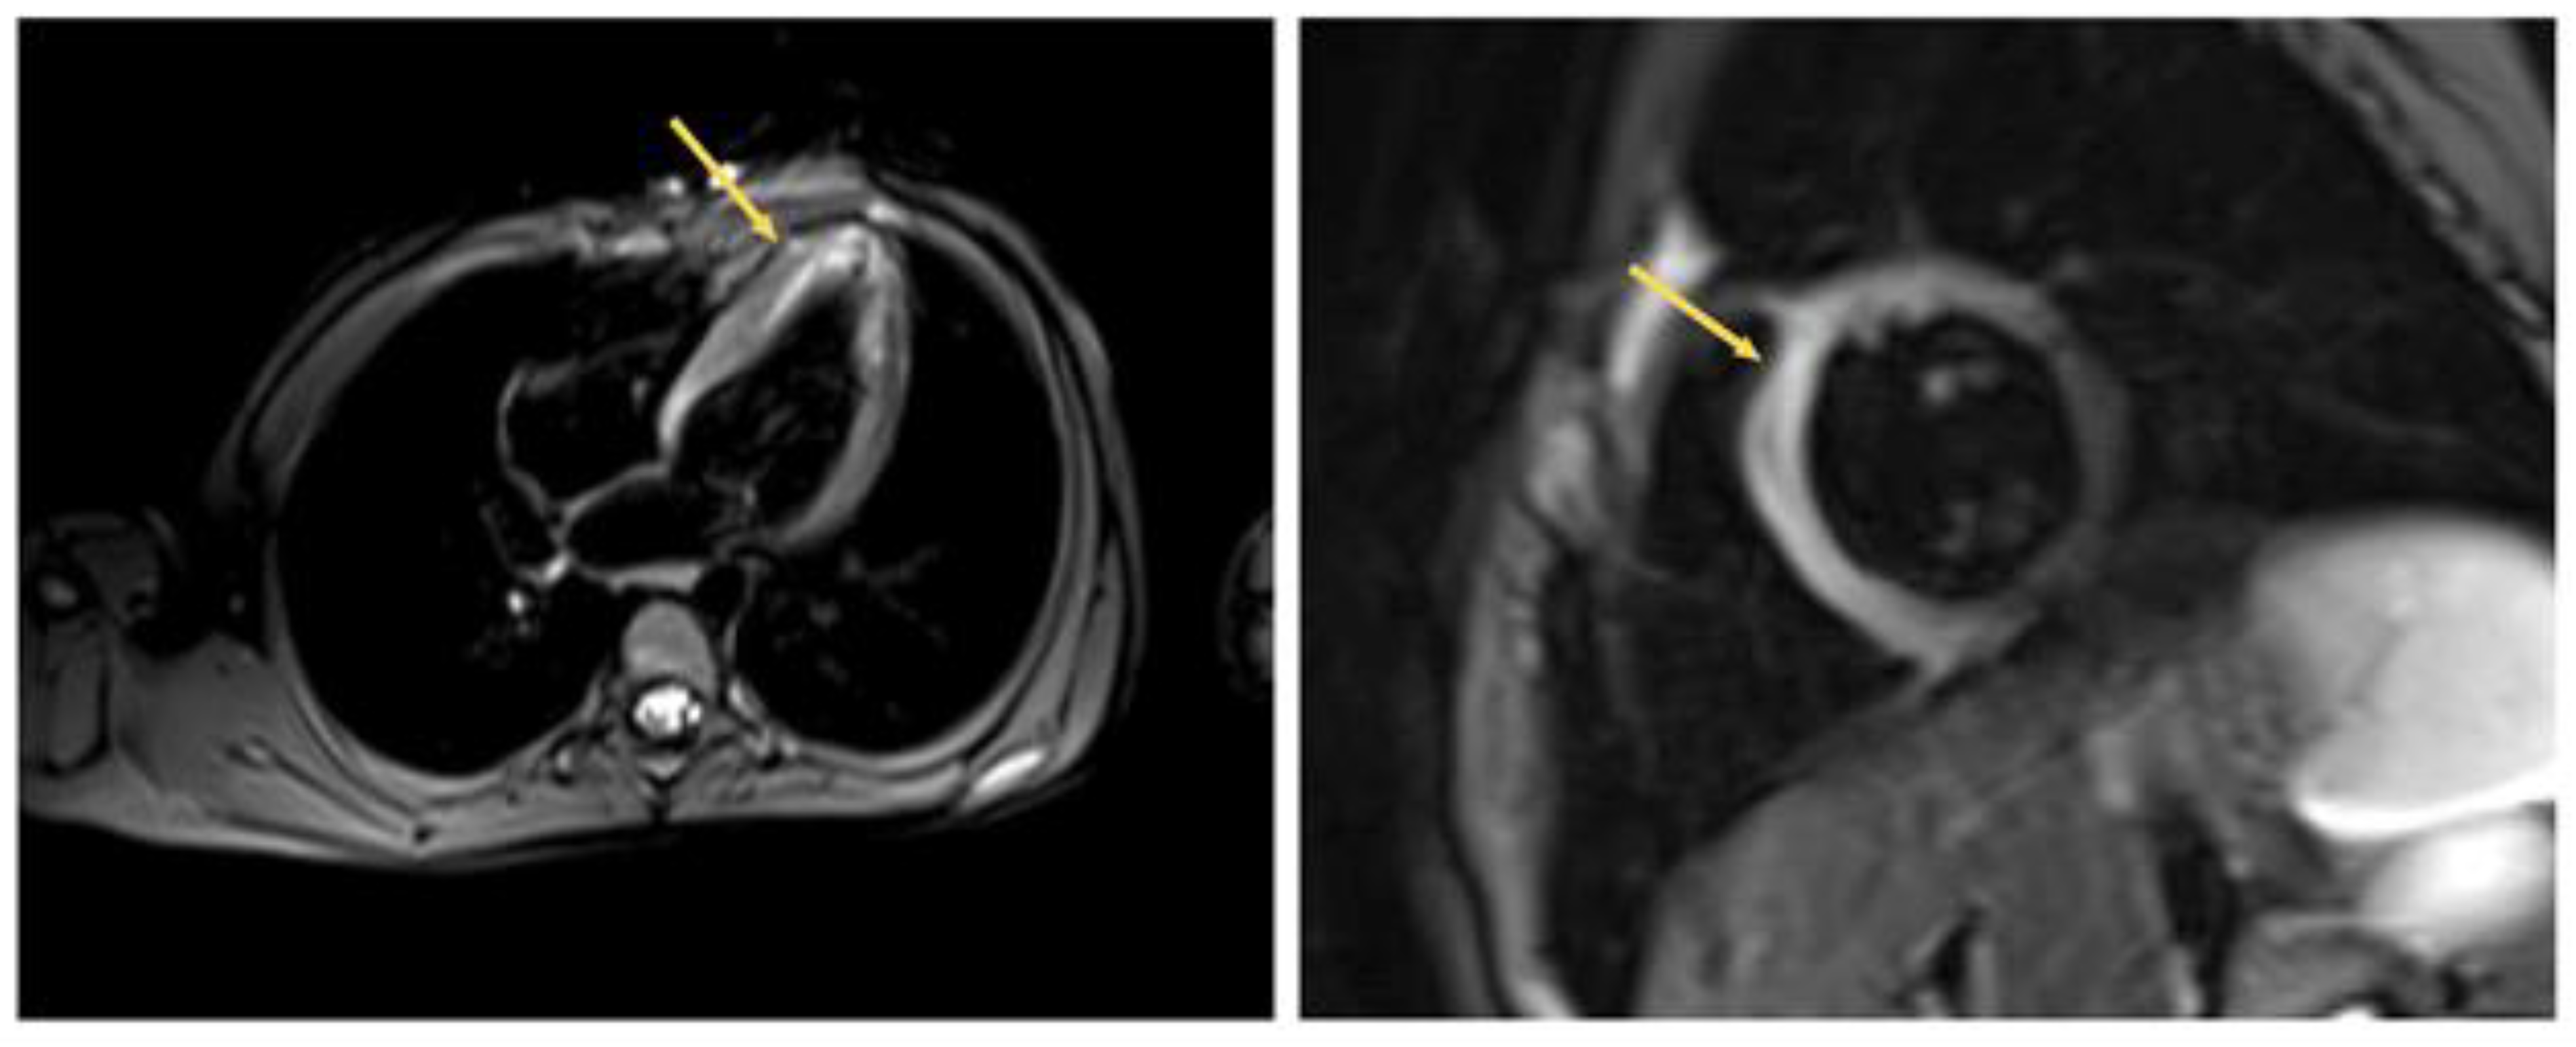

Signs of the signal enhancement on Tirm due to edema of the IVS myocardium were revealed on the heart MRI data with contrast, which indicated inflammatory changes in the myocardium three weeks later (Figure 5 and Figure 6).

Figure 5.

Heart MRI with contrast. Arrows indicate myocardial edema in the region of the interventricular septum.